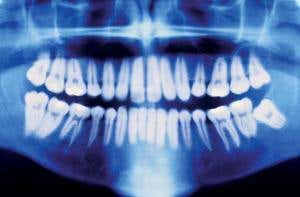

With age comes wisdom teeth (Image: UBH Trust/Getty)

Dental scans are also used to determine the maturity of wisdom teeth. These can reach full maturity as early as age 15, as late as 25, or in some cases never fully develop at all.

Unfortunately, attempts to assess age with X-ray scans of teeth or wrists are doomed to failure, according to work to be published this week in the British Medical Bulletin. The fundamental flaw with such tests is that, because children grow at widely different rates, skeletal maturity shown on X-rays – which is used to gauge age – doesn’t necessarily match chronological age. Teenagers can have adult bone structure as early as 15 or later than 20, says study author Tim Cole at University College London (UCL). He says X-rays can provide the wrong answer about whether someone is under or over 18 up to a third of the time.